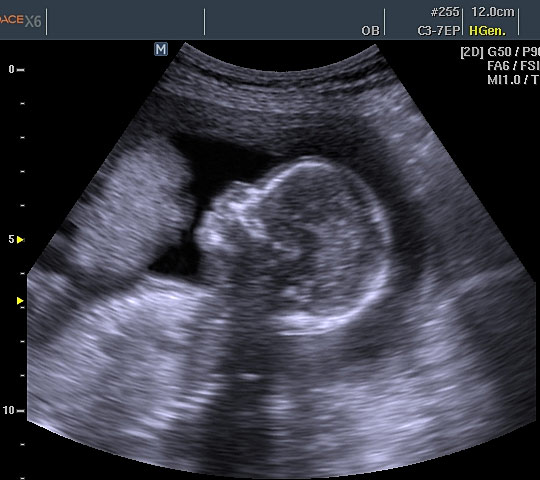

Эхограмма плода

В результате обычного, плоскостного ультразвукового исследования получают двумерное черно-белое изображение в двух измерениях — по длине и по высоте.

Таким способом диагностируют состояние околоплодных вод и внутренних органов плода: нарушения развития головного мозга, пороки сердца, почек и пр. органов. А также отслеживают динамику развития плода: рост, пропорции.